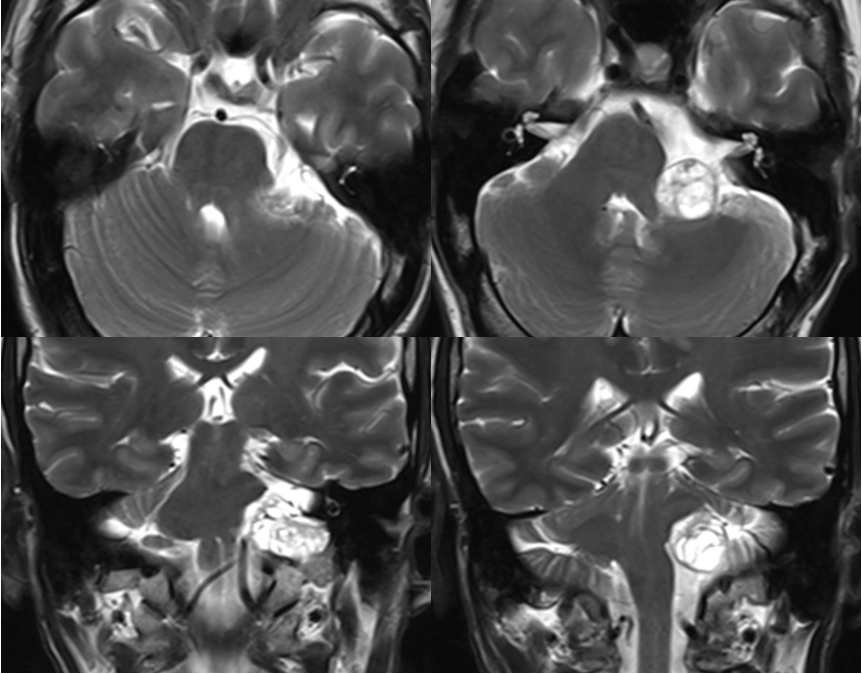

术前影像

术中过程

术后影像